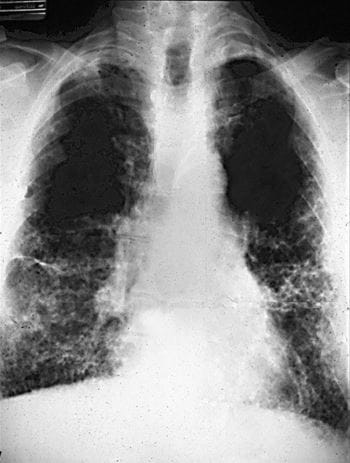

Diagnoza azbestozy opiera się na różnych badaniach i ocenie historii choroby pacjenta. Lekarz przeprowadzi wywiad z pacjentem, aby dowiedzieć się o ich narażeniu na azbest w przeszłości. Następnie zleci odpowiednie badania, takie jak badanie rentgenowskie klatki piersiowej, tomografię komputerową, bronchoskopię lub biopsję.

- Badanie rentgenowskie klatki piersiowej może dostarczyć wstępnych wskazówek dotyczących obecności zmian azbestowych w płucach.

- Tomografia komputerowa jest bardziej szczegółowym badaniem, które umożliwia dokładną wizualizację struktur płuc i okolicznych tkanek.

Azbestoza płuc, znana również jako pylica azbestowa, jest jednym z najpoważniejszych skutków długotrwałego narażenia na azbest. Powstaje w wyniku wdychania azbestowych włókien, które gromadzą się w płucach. W rezultacie powstają blizny i włóknienie płuc, co prowadzi do utraty elastyczności i zmniejszenia zdolności do oddychania. Objawy azbestozy płuc mogą obejmować duszność, kaszel, zmęczenie oraz ból w klatce piersiowej.